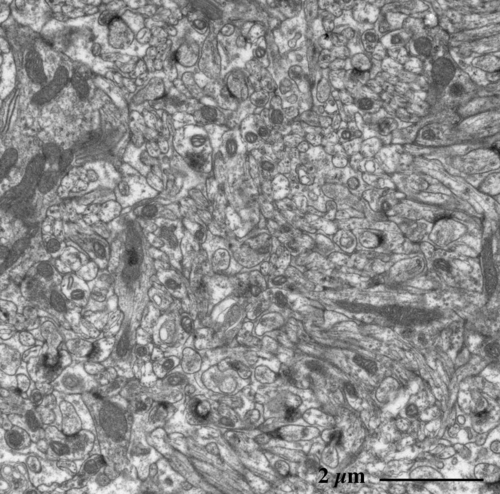

【 薄さ70 - 80 nm 超薄切片の透過型電子顕微鏡画像 】

Transmission electron microscopic image of 70 - 80 nm ultrathin section

大型でフラスコ形のプルキンエ細胞 Purkinje cell (*)

プルキンエ細胞の樹状突起

果粒層 granular layer

神経終末の密集部

シナプスの拡大像